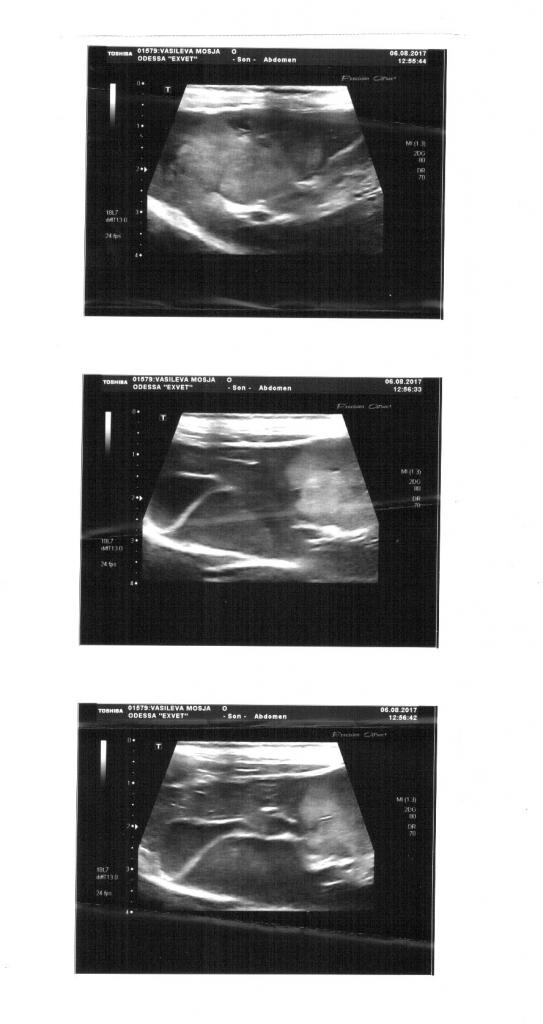

в воскресенье пошли в Эксвет к Илларионовой (по хорошему надо было сначала идти к ней, а потом уже ко всем остальным).

Если общий и биохимия нас порадовали - анализы для его возраста (коту около 8 лет)и потрепанности очень хорошие,то УЗИ огорчило невероятно. у кота опухоль в верхней левой доле печени. Причем расположена так,что добраться туда нереально(( тут вопрос с глазами отошел на второй план, надо было вообще решать,что делать дальше. кроме того у него шатались и безумно болели клыки,что не доставляло коту радости

дальше все зависило от того,есть метастазы или нет. Если есть- то просто удаляем клыки и на этом все, просто поддерживающие препараты,если нет, то тогда можно еще побороться. Рентген показал,что метастаз нету.

Изображения

• Тип файла: jpg 20170805_134903.jpg (66.5 Кб, Просмотров: 162)

• Тип файла: jpg an_1.jpg (215.4 Кб, Просмотров: 129)

• Тип файла: jpg an_3.jpg (144.4 Кб, Просмотров: 61)

• Тип файла: jpg uzi.jpg (52.6 Кб, Просмотров: 60)

• Тип файла: jpg an_2.jpg (228.3 Кб, Просмотров: 132)

• Тип файла: jpg an_4.jpg (162.6 Кб, Просмотров: 75)